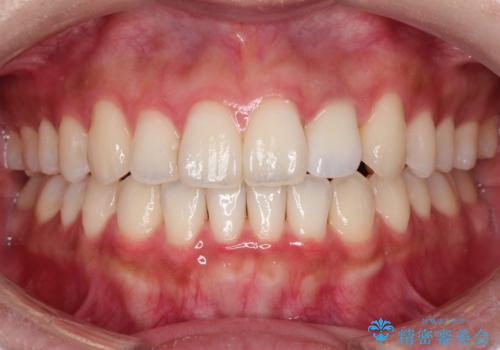

前歯の変色 オールセラミッククラウン

- 前歯の変色を主訴に来院されました。

根管治療後、オールセラミッククラウン(エクセレント)にて治療を行なっています。

オールセラミッククラウン(エクセレント)は、技工士さんが立会う事で色調や形態の相談を行うことができ、満足度の高い治療を行うことができます。